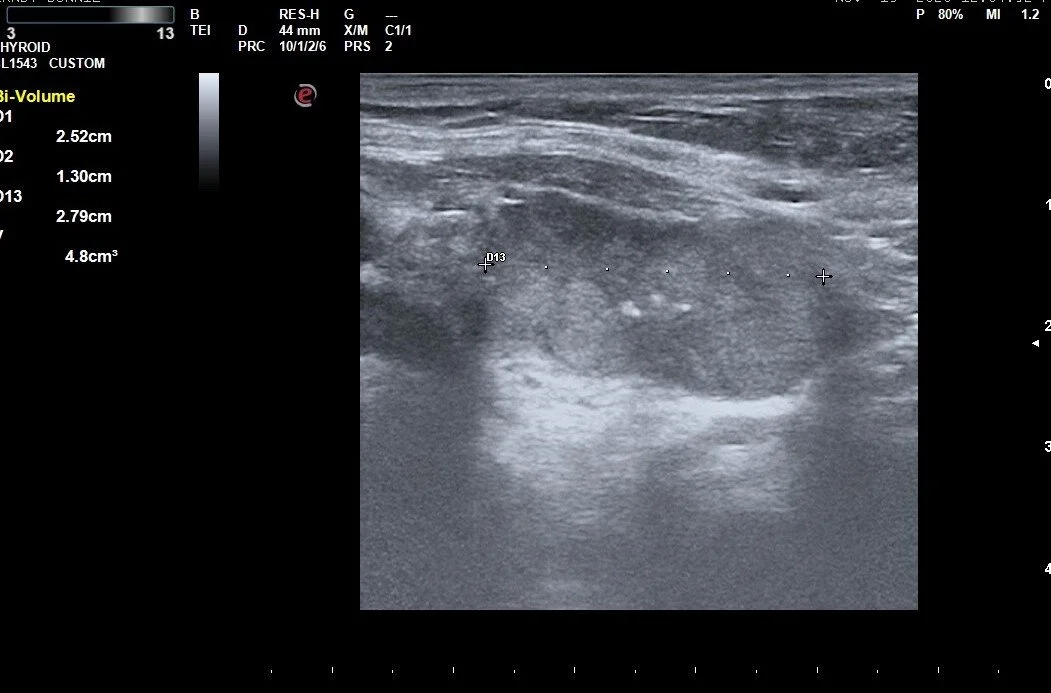

This case shows effect of 2 treatments on a large nodule and the correlation between volume reduction and normalization of thyroid levels

Ablation is accomplished by the dissipation of heat (produced by high-frequency radio waves) from the tip of a special water-cooled needle. Specialized white blood cells subsequently remove the dead nodule tissue in the weeks, and months following RFA, which causes the nodule to shrink considerably. Large-scale studies have shown an average reduction in nodule volume of approximately 60% after 3 months, and of 80% after one year, depending on the original nodule size and composition.

Most studies have suggested that nodules less than 10-12 mL in volume have a better chance of normalizing TFTs with 1 session of RFA